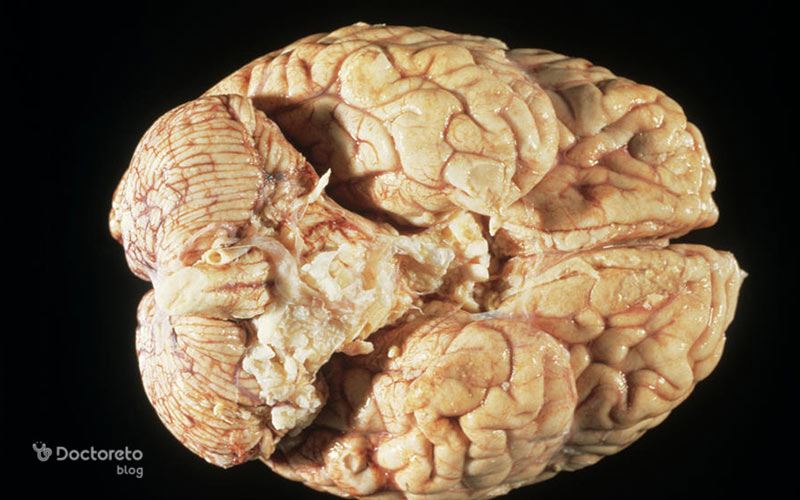

عکس تومور مغزی بدخیم در مراحل پیشرفته

در مراحل پیشرفته، تومور مغزی بدخیم معمولاً در تصاویر MRI یا سی تی اسکن بهصورت تودهای بزرگ، نامنظم و با مرزهای نامشخص دیده میشود. این تومورها اغلب باعث فشار زیاد بر بافتهای اطراف مغز، تورم و جابهجایی ساختارهای طبیعی مغز میشوند. در تصاویر MRI، ممکن است بخشهایی از تومور که دچار نکروز شدهاند، قابل مشاهده باشند و نواحی اطراف آن معمولاً با شدت سیگنال غیرطبیعی نشان داده میشوند.

در این مرحله، بیماران معمولاً علائم شدیدتری مانند سردرد مداوم، تشنج، اختلال در گفتار یا بینایی و تغییرات شخصیتی را تجربه میکنند. تصاویر مراحل پیشرفته معمولاً برای برنامهریزی درمانهای ترکیبی مانند جراحی، رادیوتراپی و شیمیدرمانی استفاده میشوند. تشخیص دقیق از روی عکسها به پزشکان کمک میکند تا میزان گسترش تومور و درگیری نواحی حیاتی مغز را مشخص کرده و بهترین رویکرد درمانی را انتخاب کنند.